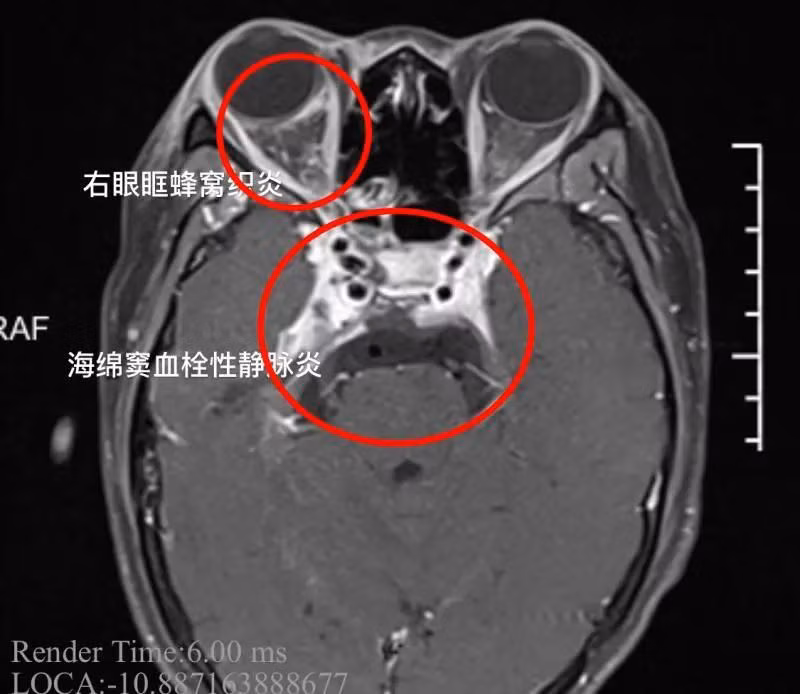

Ảnh chụp CT hộp sọ của Tiểu Dương. Trong ảnh: Vòng tròn đỏ to thể hiện huyết khối xoang hoang gây viêm tắc tĩnh mạch, vòng tròn đỏ nhỏ thể hiện ảnh hưởng của viêm tắc tĩnh mạch gây sưng tấy và khiến mắt phải của Tiểu Dương không thể mở được (Ảnh: Tin tức buổi tối Ninh Ba).

Sau khi chẩn đoán, các bác sĩ tại Khoa Thần kinh chẩn đoán Tiểu Dương bị viêm tắc tĩnh mạch xoang hang, một bệnh nhiễm trùng nội sọ nghiêm trọng, nếu không được điều trị kịp thời có thể dẫn đến tử vong.

Khi Tiểu Dương mới đến, tình trạng của cô đã tương đối nghiêm trọng, thân nhiệt cơ thể luôn duy trì trên 39 độ C. Mắt phải của cô gái bị lồi, mắt không thể xoay, đồng tử giãn, phản xạ ánh sáng biến mất và nhiều nhóm dây thần kinh sọ não bị ảnh hưởng, thể hiện dấu hiệu nhiễm trùng xoang nặng.

Đồng thời, các bác sĩ cũng nhận thấy, Tiểu Dương bị kích thích màng não, viêm xoang hang đã lan rộng, xuất hiện viêm màng não và tiếp tục tiến triển có thể nguy hiểm đến tính mạng bất cứ lúc nào.